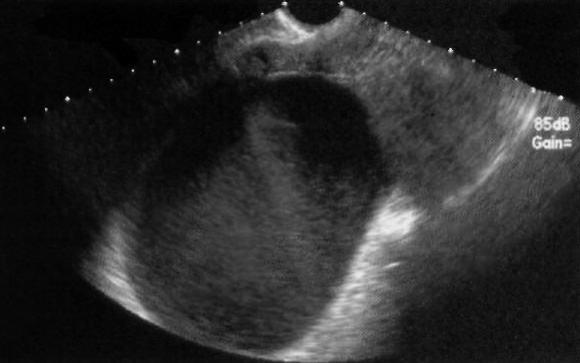

УЗИ позволяет визуализировать множественные фолликулы – эхогенные полости небольших размеров, локализованные внутри яичников (фото 1).

Фото 1. Продольный вид яичника с фолликулами в виде анэхогенных образований